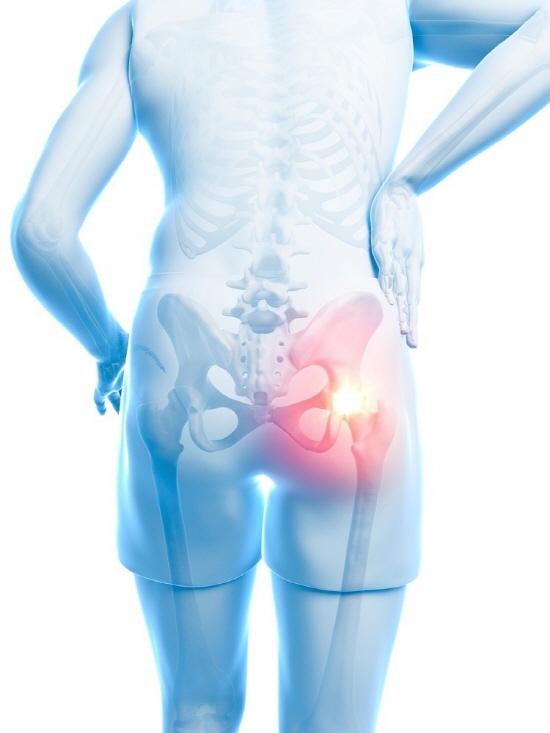

고관절 통증 증상

고관절 통증 증상에 대해 알아보겠습니다.

좌골 신경통에 의해서 고관절에 통증이 올 수 있습니다. 좌골 신경의 자극 또는 염증에 의하여 다리가 아픈 경우인데 좌골 안쪽으로 신경이 다리로 오기 때문에 좌골신경통이 있으면 고관절에도 통증이 옵니다. 좌골신경통에 의하면 등 아래쪽부터 엉덩이와 다리 뒤쪽 부분까지 통증이 옵니다.